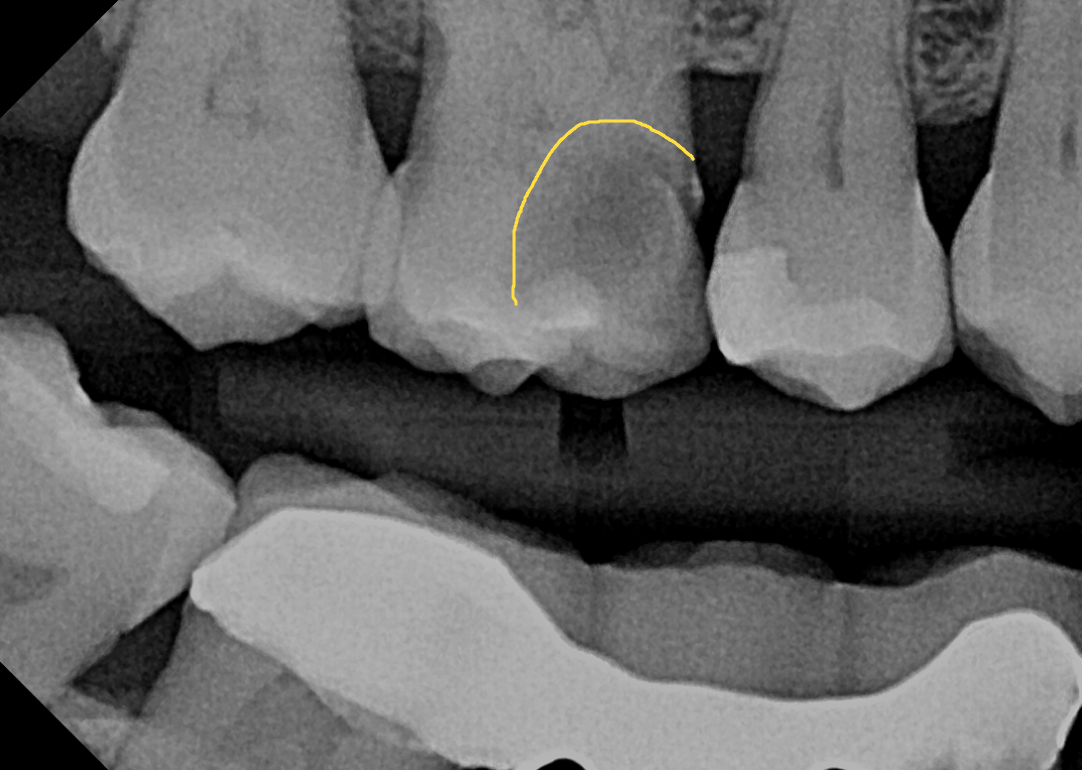

Patient Le Laroi presented to my dental office on 5/13/24 with a broken tooth on the top right. Patient was not in any pain, but there was a large hole in the tooth that would need to be examined. Because the hole in the tooth was so big and so deep, I assumed the tooth was necrotic, or dead. First we took the necessary X-rays: A panoramic radiograph (which gives us a broad view of all the teeth), and a bitewing radiograph (which is an up close, detailed view of the tooth). Upon examination, it was determined that the broken tooth is a first molar, also known as tooth #3. The X-rays revealed a large cavitated carious lesion, extending into the pulp chamber of the tooth where the nerve resides. This appears on the X-ray as a large black shadow on a tooth. Usually, once decay has reached the pulp chamber, either the nerve becomes symptomatic and painful, or it dies all together. To confirm my assumptions, I performed what we call a ‘vitality’ or ‘cold’ test to determine if the tooth is alive or not. I was not expecting Le to feel the cold temperature that was applied to the tooth, but she did! The tooth was not necrotic as it appeared, it was alive and well! When Le asked me if I thought it was a miracle, I said, “sure it is.” Miracles can come in all shapes and sizes, and in this case, there is no clinical explanation as to why this tooth is alive and well without any symptoms or sensitivity.All Glory and Praise to God!

X-ray picture of the tooth with the cavity marked: